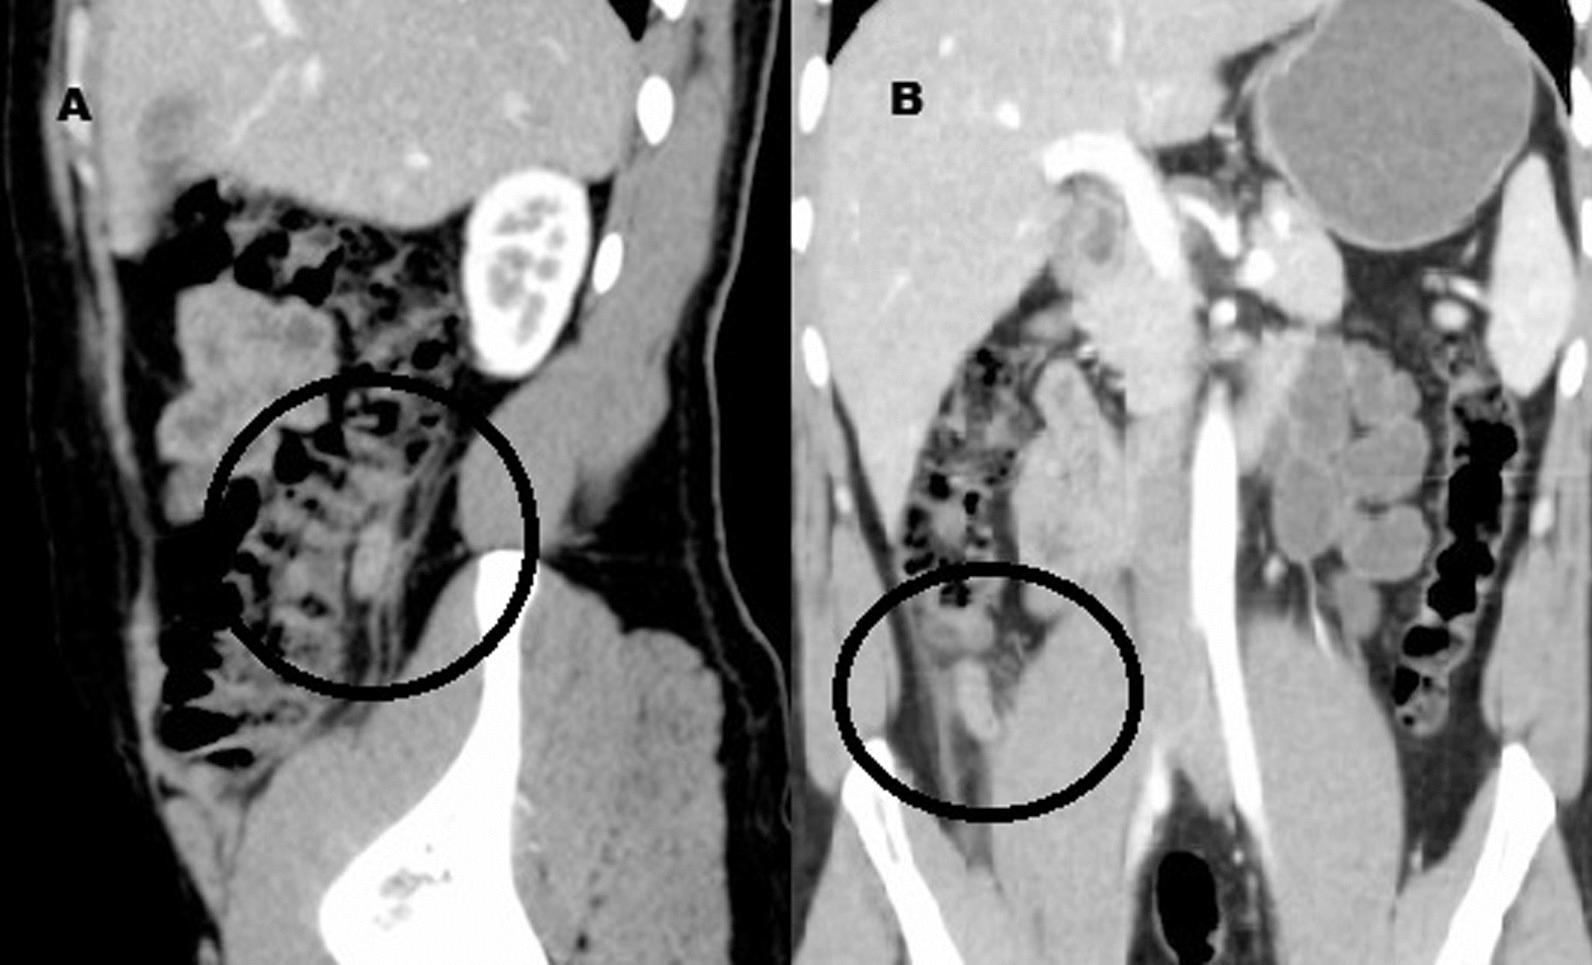

We present a case of 29-years old Egyptian male patient with history of appendectomy one and half year before presenting to the emergency department with recurrent acute abdominal pain that was linked to duplex appendicitis abnormally emerged from the mid-ascending colon. The first episode was treated conservatively considering atypical right colon diverticulitis as a potential differential diagnosis. Seven months later the patient was treated by laparoscopic appendectomy and experienced an uneventful pot-operative course.

我们报告了 1 例 29 岁埃及男性患者,他在急诊就诊前 1 年半曾行阑尾切除术,反复出现急性腹痛,与异常起源于升结肠中段的双阑尾有关。第一次发作时,由于考虑到不典型的右结肠憩室炎是潜在的鉴别诊断,因此采用保守治疗。7 个月后,患者接受了腹腔镜阑尾切除术,术后恢复顺利。